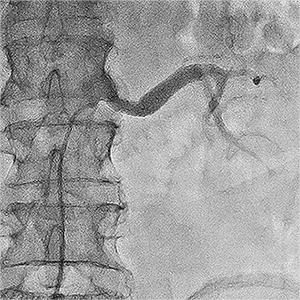

Приклади ангіограм до та після дилятації:

стеноз лівої клубової артерії    балон, роздутий в зоні стенозу    відновлення отвору клубової артерії

Значний стеноз лівої

наружної клубової артерії

Балон-катетер,

роздутий в зоні стенозу

Отвір артерії відновлено на 80%